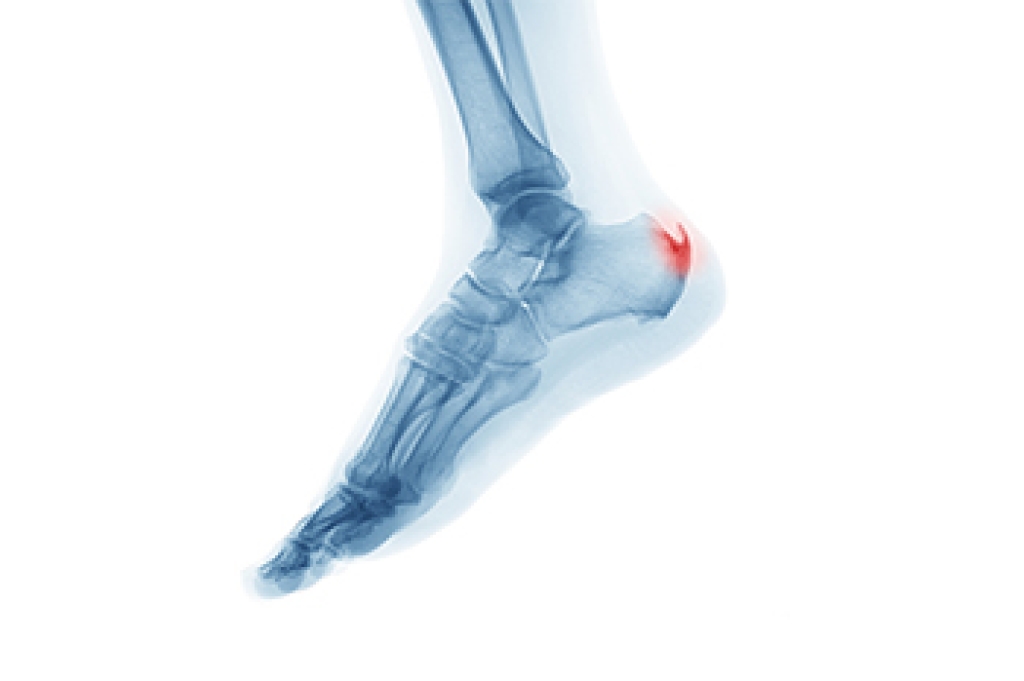

Diagnosis

A chiropodist will ask questions about your personal and family medical history, followed by an examination of the affected joint. Laboratory tests and x-rays are sometimes ordered to determine if the inflammation is caused by something other than gout. A sample of fluid taken from your joint can show whether it contains uric acid.